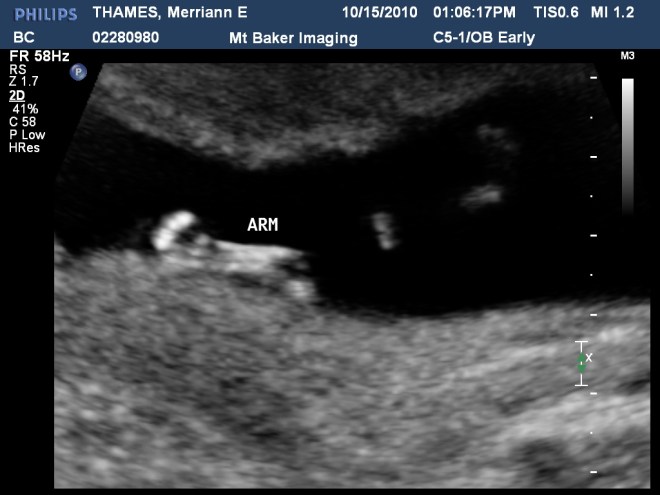

That’s right folks. We’re having a baby! I am due April 27. I had no idea how far along I was so we headed in for an ultrasound. I was already already over 12 weeks! Not that I hadn’t known at all. I have the constant nausea thing going on. But it is still nice when all things are confirmed and your 1/3 done. We looking forward to a spring baby. Warmer days, less bundling and another family member to share a spring B-day with Greg.